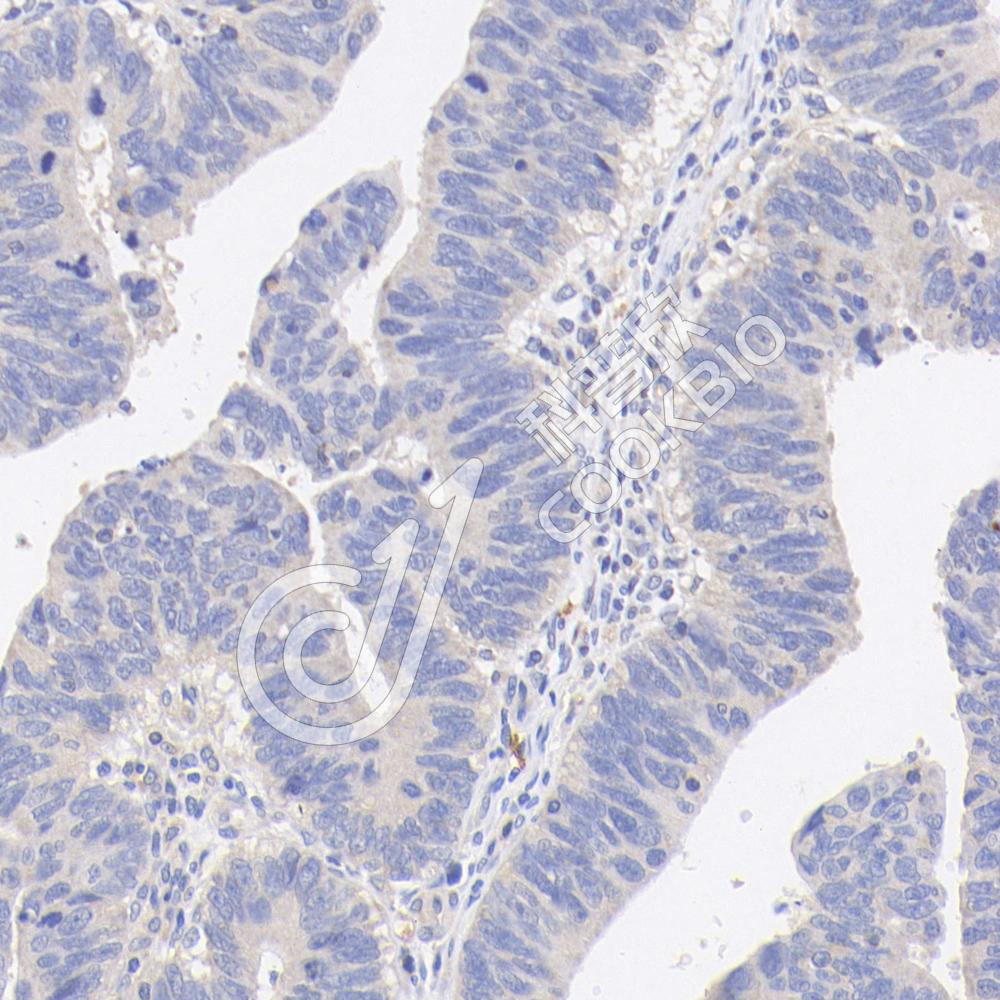

IHC检测CD63蛋白(货号 K1347136).

样品: 大鼠脾, 4%多聚甲醛 (货号KSG1101) 固定12-24小时.

抗原修复: 柠檬酸抗原修复液(干粉, pH 6.0) (KSG1201), 98℃, 20分钟.

—抗: 1: 1000稀释, 4℃ 孵育过夜.

二抗: S-vision免疫组化多聚二抗(山羊抗兔),即用型 (货号KB3906), 室温孵育20分钟.